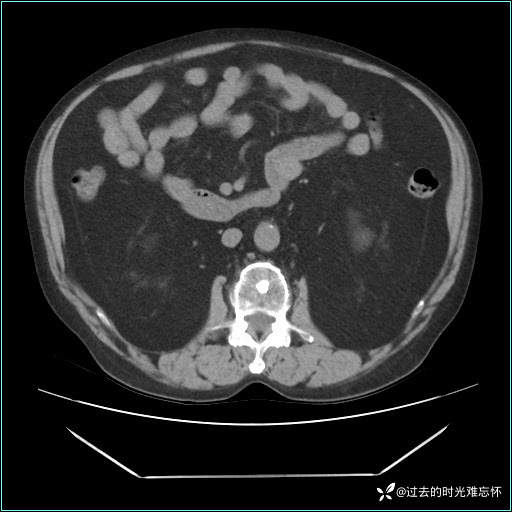

男子肚子大如孕晚期,一看腹腔竟被脂肪填满了...

患者男,71 岁,因「反复腹痛腹胀 1 月」入院。

现病史:患者 1 月前无明显诱因下出现腹痛腹胀症状,腹痛呈隐痛,当时未予以重视,后症状有所加重,常在进食辛辣刺激油腻等食物后出现腹痛,口服药物治疗症状能得到控制,病情控制一般。现为求诊治来我院,拟“腹痛”入院。病程中患者神志清楚,精神一般,无咳嗽咳痰,无恶心呕吐,近期体重无明显变化。